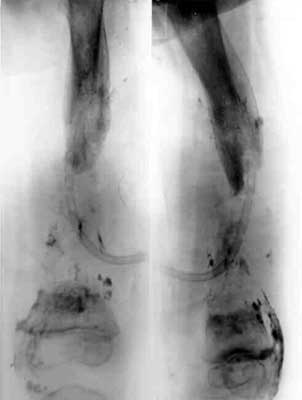

Bowlegs and knock-knees

Pffd in children